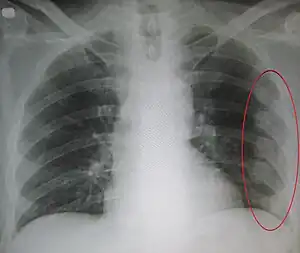

Right sided pneumothorax and rib fractures

| An X ray showing multiple old fractured ribs of the person's left side as marked by the oval. | |